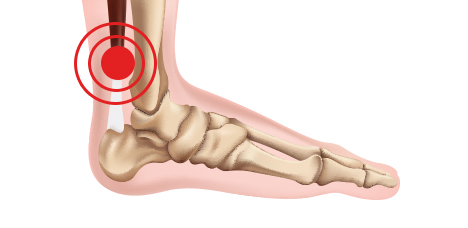

아킬레스건염

아킬레스 건 부위에 염증이 생긴 질환

족저근막염

발바닥에 있는 족저근육막에 염증이 생기는 질환